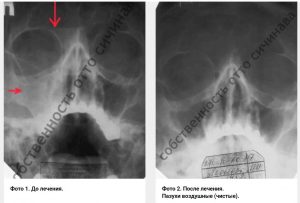

Хронический фронтит – это гнойно воспалительное заболевание лобных пазух. Обострение которого чревато развитием заболеванием головного мозга. Не редко такие обострения могу привести к летальному исходу.

Традиционный процесс лечения фронтит происходит следующем способом – введением через нос в лобную пазуху вводится канюля с помощью которой происходит промывание пазухи. Однако, кроме такого метода, в традиционной медицине прибегают так же к другой, более жесткой методике, лечения в виде трепанопункции лобной пазухи. Над надбровной дугой осуществляется небольшой надрез кожи, а затем костную ткань засверливают с целью создания отверстия для установки пластиковой трубочки, через которую промывают пазуху. Как правило, таким пациентам внутривенно капельно вводят антибиотики в сочетания с гормональными средствами

В нашей клинике такие методики считаются варварскими. Так-как есть методики лечения без операций, которую как правило, не применяют в классической медицине.

В нашей клиники метод лечения хронического фронтита отличается естественными физиологическими процедурами:

Таким образом нам удалось вылечить несколько тысяч больных обреченных на хирургическое вмешательство, чему в подтверждения представлены видео отзывы нашим пациентов.